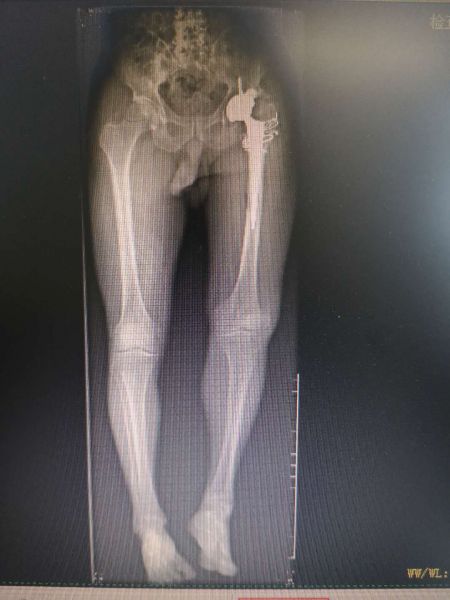

患者慕名找到湘西州人民医院骨一科主任赵峻主任医师,希望通过赵峻主任医师的治疗,能够自由行走,不再受疼痛的困扰。赵峻主任医师带领其团队,对患者进行仔细的体格检查,并仔细阅读了患者的相关影像学资料,发现患者左髋关节活动度已完全尚失,左下肢明显外旋畸形,且左下肢较对侧短了近6cm。经赵峻主任医师及其团队讨论后,制定详细的手术方案。完善术前检查后,于4月19日在麻醉科及手术室共同协助下行左侧人工髋关节置换术,虽然术前已经对术中可能出现的困难进行了充分的准备,但手术的复杂程度远远超过预期。面对术中各种挑战,赵峻主任带领其团队,沉着应对,最终历时4个小时,顺利完成手术。术后行X线片检查提示患者左下肢长度较前明显恢复,且在骨一科全体医护人员的精心指导下积极行功能锻炼,患者左侧髋关节活动度明显改善。最终患者健康出院。

患者术前X线片 患者术后X线片